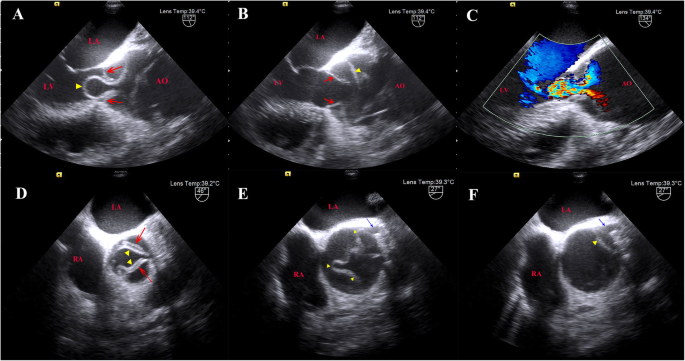

On this admission, the patient suffered from chest pain for about 1 h. The blood pressure was 143/42 mmHg, and there was no difference between two arms. He was conscious and neurological examination showed no abnormalities. Electrocardiography showed ST segment depression in leads I, aVL and V4–6, and preoperative hsTnT level was elevated to 45.60 ng/L (under 14 ng/L is normal). Contrast-enhanced computed tomography (CECT) revealed a Stanford type A aortic dissection with circumferential dissection of ascending aorta, and the proximal intimal flap prolapsed into the left ventricle outflow tract (LVOT) (Fig. 1). The coronary arteries arising from the true aortic lumen were not involved in the dissection. The dissection extended distally to brachiocephalic trunk, bilateral common carotid artery, and left subclavian artery, and ended at right common iliac artery. TTE indicated aortic dissection with a proximal intimal flap moving in and out of the LVOT in synchronicity with the cardiac cycle causing severe AR. He was therefore scheduled for urgent surgical treatment. Intraoperative TEE further confirmed a balloon-like intimal flap prolapsing into LVOT during diastole, which interfered with aortic valve cusp mobility, causing severe AR (Fig. 2, Supplementary material video 1–4). However, regurgitant flow was concentrated in a balloon-like intimal flap, concealing the degree of preexisting aortic insufficiency. The LV was dilated to 7.0 cm in diameter with mild left ventricular wall hypertrophy, and mild left ventricular lateral wall motion abnormalities. The ascending aorta was severely involved by dissection and therefore, cardiopulmonary bypass was instituted by cannulation of right atrium and right axillary artery combined with right femoral artery. Surgical inspection confirmed that the intima of the ascending aorta had been torn away through almost all of its circumference and the dissection extended proximally to below the level of coronary arteries. However, the coronary arteries and aortic valve annulus were not involved with dissection. The aortic valve commissures were intact, and the aortic valve leaflets were degenerated with mild thickening and without prolapse and deformity. Bentall procedure (aortic valve replacement with ascending aorta graft implantation) and Sun’s procedure (total arch replacement using tetrafurcate graft with stented elephant trunk implantation) were performed. During hypothermic circulatory arrest, nasoparyngeal temperature was 25 °C and antegrade cerebral perfusion by combining right axillary artery with left common carotid artery was selected for cerebral protection. The total cardiopulmonary bypass time was 244 min, aortic cross-clamping time was 138 min and circulatory arrest time was 17 min. The surgery was uneventful, and the patient was discharged on the 7th postoperative day after a smooth recovery. Histopathological analysis revealed myxoid degeneration of aortic valve and ascending aortic wall.

Severe AR due to prolapse of an intimal flap into LVOT of acute aortic dissection is a rare event. The hypothesis proposed by Chow et al. states that aortic root dilation may be the prerequisite condition of prolapsed intimal flap-induced AR, in this case resulting in the phenomenon of “regurgitation begets regurgitation” [3]. The characteristics of the patient in our case were consistent with this hypothesis. The structure and function of aortic valve were evaluated carefully in real time by midesophageal long axis and short axis views. However, the degree of preexisting aortic insufficiency was covered up by the prolapsed intimal flap-induced AR. As a result, surgeons are forced to inspect aortic valve directly in a state with aorta and heart empty and flaccid after commencing cardiopulmonary bypass [13]. Although experienced surgeons may determine whether the replacement or repair of aortic valve is or is not based on direct inspection alone of aortic valve, it is preferable for surgeons to evaluate the aortic valve in a physiologic state with aorta full and heart beating [13].